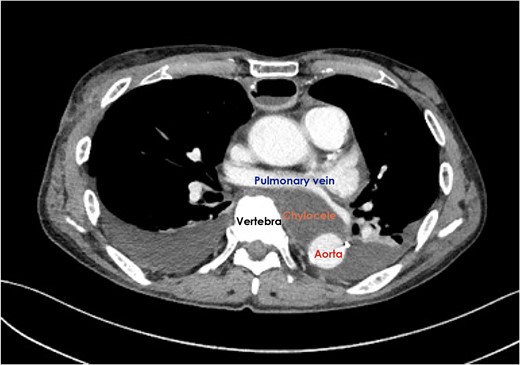

A 75-year-old male received neoadjuvant chemotherapy for locally advanced squamous cell carcinoma of the mid-thoracic esophagus, followed by right transthoracic esophagectomy with extended mediastinal lymphadenectomy. Cardiac tamponade developed on postoperative Days 1 and 13, for which emergency ultrasound-guided drainage was required. Pericardial drainage fluid became chylous after administration of polymeric formula. A computed tomography scan demonstrated the presence of a retrocardiac fluid collection, encompassed by the left pulmonary vein and left atrium, descending aorta and vertebral column. Based on these findings, the diagnosis of chylopericardial tamponade communicating with a posterior mediastinal chylocele was made. The ligation of the thoracic duct was successfully performed via the left-sided thoracoscopic approach on postoperative Day 20 and the clinical course after the second operation was uneventful. The possible mechanisms of this exceptionally rare complication after esophagectomy were discussed.

Enteral feeding with low-fat elemental formula was commenced in the morning on postoperative Day (POD) 1; however, hemodynamic instability suddenly developed in the afternoon on the same day. Echocardiography performed during cardiopulmonary resuscitation demonstrated massive pericardial effusion. Emergency ultrasound-guided drainage was performed via the subxyphoid approach; 350 mL of serous fluid was drained, and the patient’s hemodynamic status dramatically improved. After changing to fat-containing polymeric formula on POD 5, a small amount of chylous fluid was contained in the pericardial drainage fluid, but not in the bilateral pleural drainage fluid. Because the chylous fluid disappeared immediately after returning to the elemental formula, the right pleural, pericardial, and left pleural drains were removed sequentially. A fat-reduced diet was given to the patient; however, the cardiac tamponade relapsed and the pericardial drain was re-inserted on POD 13. A computed tomography scan demonstrated the presence of a retrocardiac fluid collection, encompassed by the left pulmonary vein and left atrium, descending aorta and vertebral column (Fig. 1). The initial pericardial drainage fluid was serous, but it changed to chylous again after a challenge with polymeric formula. Under the diagnosis of chylopericardial tamponade communicating with a posterior mediastinal chylocele, surgical exploration was performed via the left-sided thoracoscopic approach on POD 20. A chyle leak from a tributary of the thoracic duct was easily recognized because of the administration of polymeric formula immediately before surgery. The leak was stopped with surgical clips. A pericardial hole, which had been made during the esophagectomy, was confirmed to be close to the leakage point (Fig. 2). The hole was left open and a closed suction drain was placed in the posterior mediastinum.

Computed tomography scan demonstrated the presence of a retrocardiac fluid collection when the cardiac tamponade relapsed.

The anatomical characteristics of this patient should be considered when discussing the development of this exceptionally rare complication. As shown in Fig. 1, the descending aorta was located dorsally in the left thoracic cavity; therefore, a space was encompassed by the left pulmonary vein and atrium, descending aorta and vertebral column. A bulky esophageal tumor occupied this space before the operation, while a chylocele replaced the tumor after it was removed. As reported by Rottoli et al. [2], chylous fluid would usually drain into the right thoracic cavity, even if a chylocele developed in the posterior mediastinum. Interestingly, vertebral column prevented chylous fluid from draining into the right thoracic cavity in this patient; therefore, no chyle drainage from the right chest tube was seen throughout the clinical course. Moreover, no chylous fluid drained into the left thoracic cavity either, although the left mediastinal pleura was partially resected with tumor of the mid-thoracic esophagus at the initial operation. The second operation revealed that the opened pleura was already covered by the left lung, which tightly adhered to the descending aorta. Because of this completely isolated space, increased chylous fluid would flow into the hypobaric pericardial space through a small hole in the pericardium.